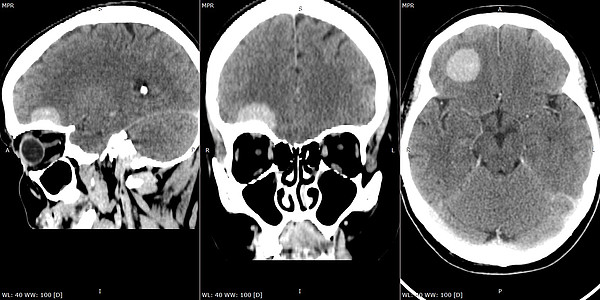

Недавно специалисты КОКБ применили технологию keyhole при оперативном лечениии жительницы Кировской области. У нее нашли объемное образование основания черепа. Опухоль извлекли через разрез вдоль брови, длиной всего в 3 сантиметра. Подход к опухоли осуществлялся по основанию черепа, то есть в пространстве между мозгом и костными структурами.

– Для расчета оптимальной траектории использовалась нейронавигация, позволившая точно определить локализацию опухоли и свести к минимуму повреждение окружающего мозгового вещества. У пациентки сохранены все двигательные, чувствительные, мнестические функции, кроме того достигнут и хороший косметический результат, – сообщил заведующий отделением.